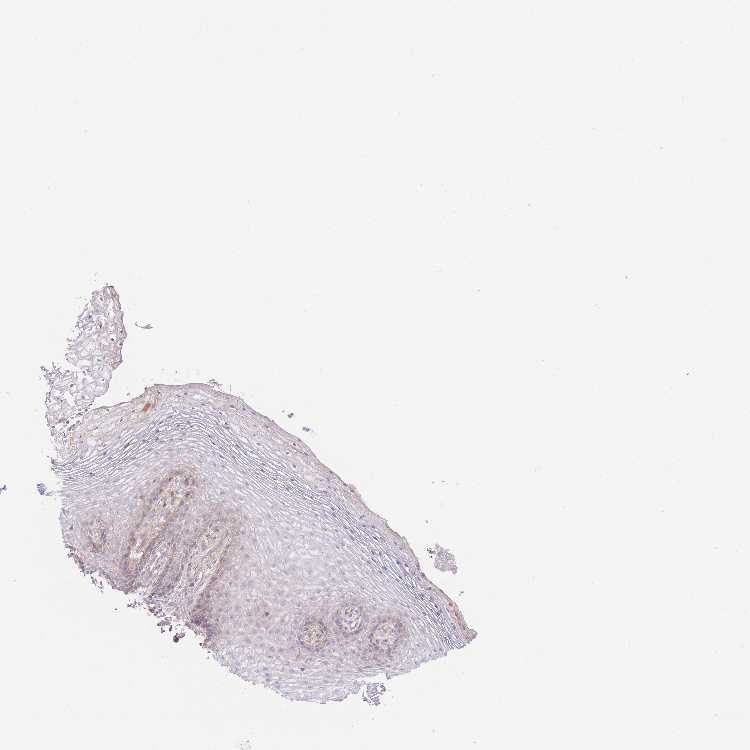

LIPH